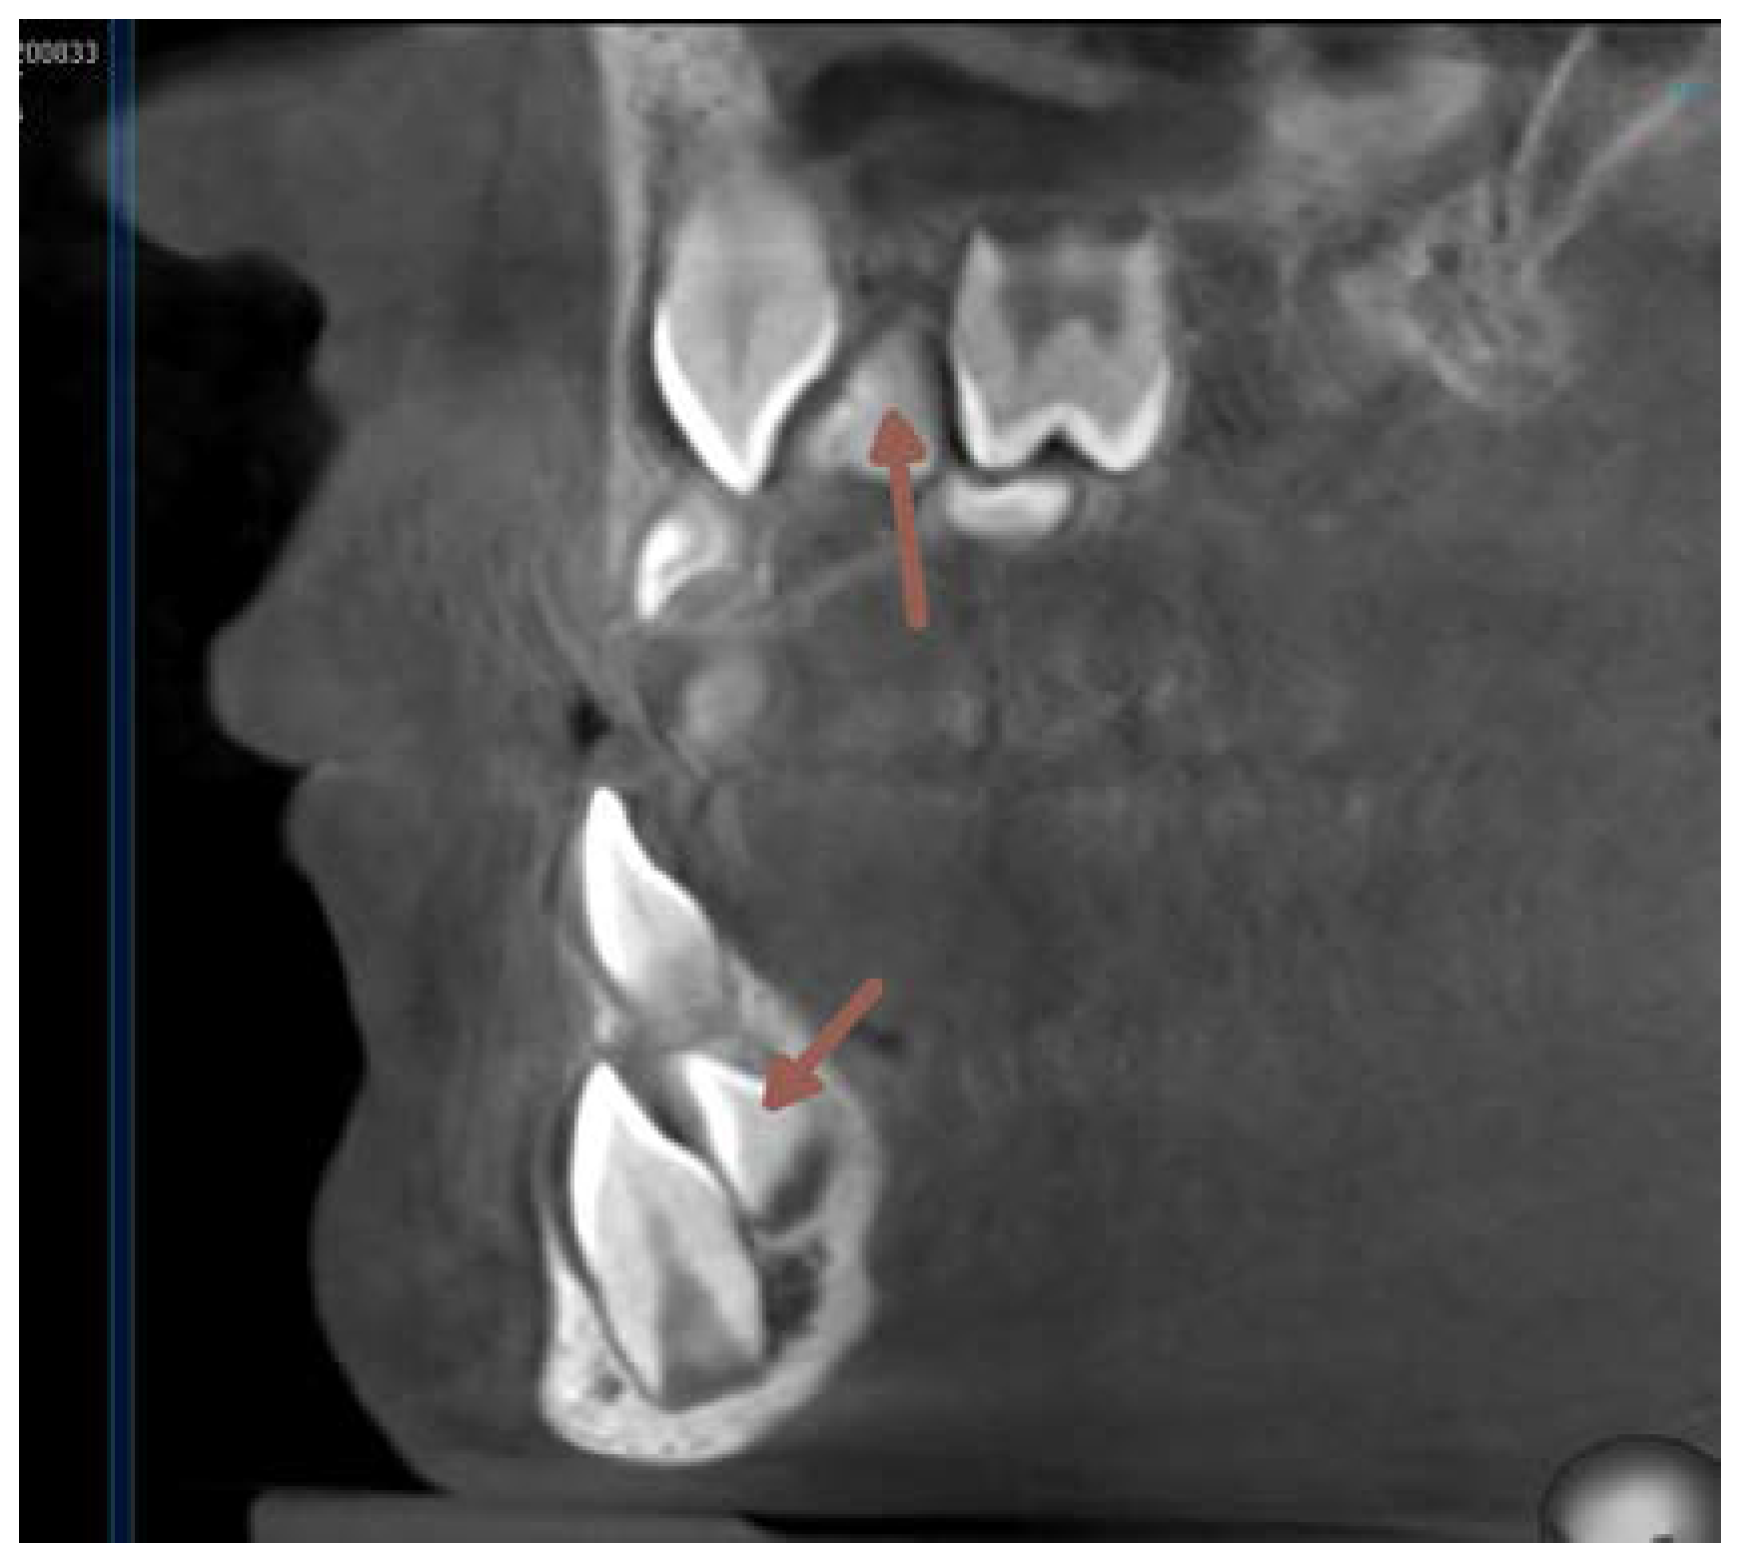

At this time the 33 and 43 were slowing down their eruption, therefore another surgical intervention was needed. Another CBCT scan image was necessary to prove the proximity of the crowns of the lower canines to the apical area of the lower lateral incisors. (Figure 15).

Figure 15. CBCT transverse section on the level of lower incisors - August 2021.